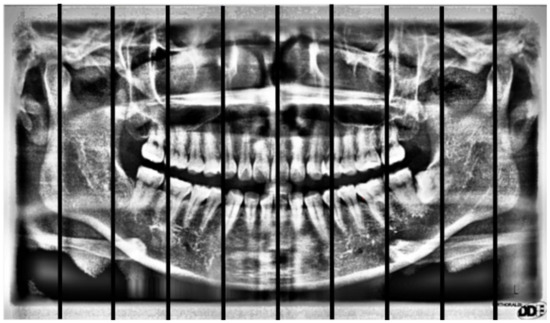

2.2. Image Segmentation

2.2.3. Positioning Numbers